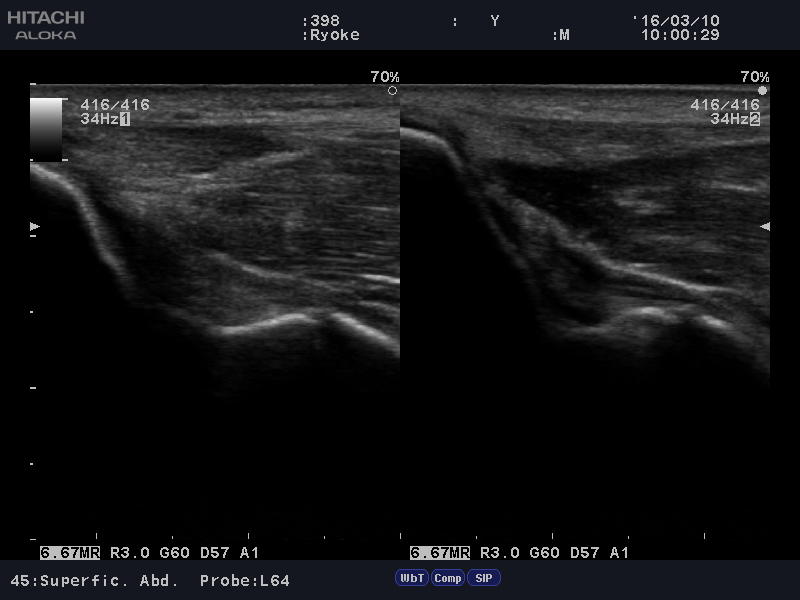

テニス肘はバックハンドの連続で肘の外側上顆を痛めるタイプと、

フォアハンドで肘の内側上顆を痛めるタイプがあります。

発生機序はボールの衝撃によって、前腕の筋肉の付着部で、

炎症を起こし、痛みを発生させるという原理。

「まる接骨院」では触診、視診、徒手検査後、

「超音波観察装置」で痛めてる場所、深さ、状態を確認し、

適格に治療を行って参ります。